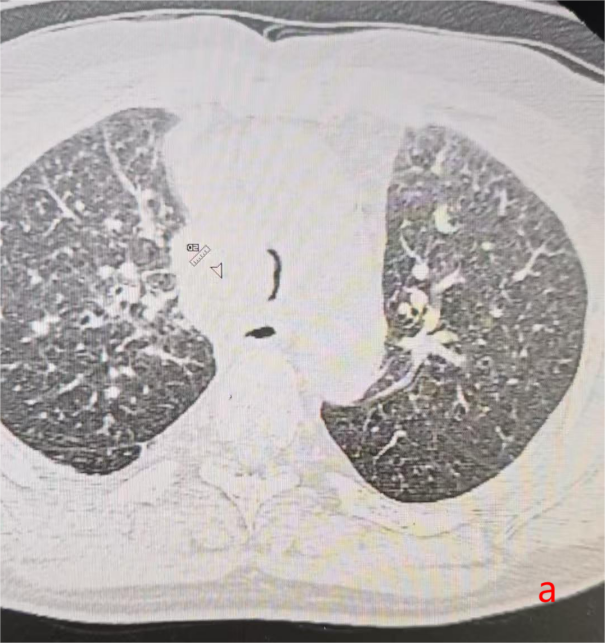

时间回到2024年11月,W先生因长期咳嗽咳痰就医检查,经胸部CT、气管镜及病理活检等一系列检查后,最终被确诊为右肺恶性肿瘤(鳞癌Ⅳ期),还合并肺内转移、纵隔淋巴结继发恶性肿瘤等问题。在多学科团队评估后,治疗按计划推进,后续拟开展胸部肿瘤放疗。

意外却在2025年9月悄然发生。当时W先生正在外院准备接受放疗,期间呼吸困难症状急剧加重,不仅无法耐受下床活动,还伴随咳嗽咳白黏痰。紧急复查CT显示,他的气管下段已出现重度狭窄,这一状况不仅严重威胁生命安全,也让原本的放疗计划因风险过高而难以实施。危急时刻,W先生前往温岭市第一人民医院寻求进一步救治。

2025年10月10日,手术在全麻下顺利开展。医护团队通过支气管镜的精准引导,将支架成功植入患者气管狭窄部位,整个过程平稳有序。术后奇迹很快显现:W先生的呼吸困难症状当场明显缓解,复查胸片提示气道下段通畅度显著改善,没过多久便能正常进行日常活动。短暂恢复后,他顺利返回继续接受胸部肿瘤放疗,整个放疗过程进展顺利,胸部肿瘤明显缩小。